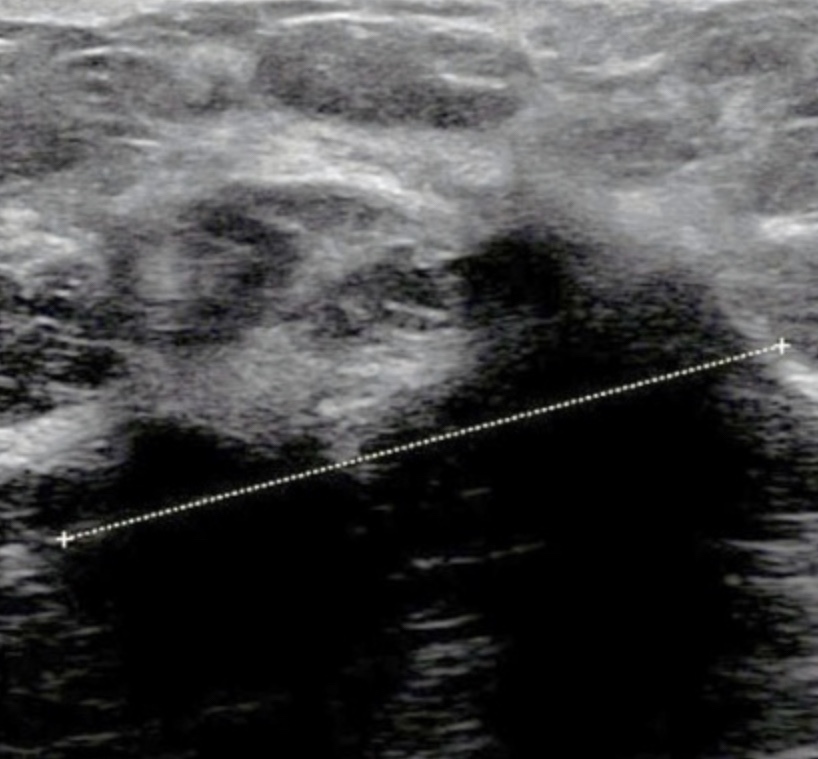

Hand-held ultrasound image

• However, the associated connective tissue response:

• Makes this type of cancer quite visible with ultrasound